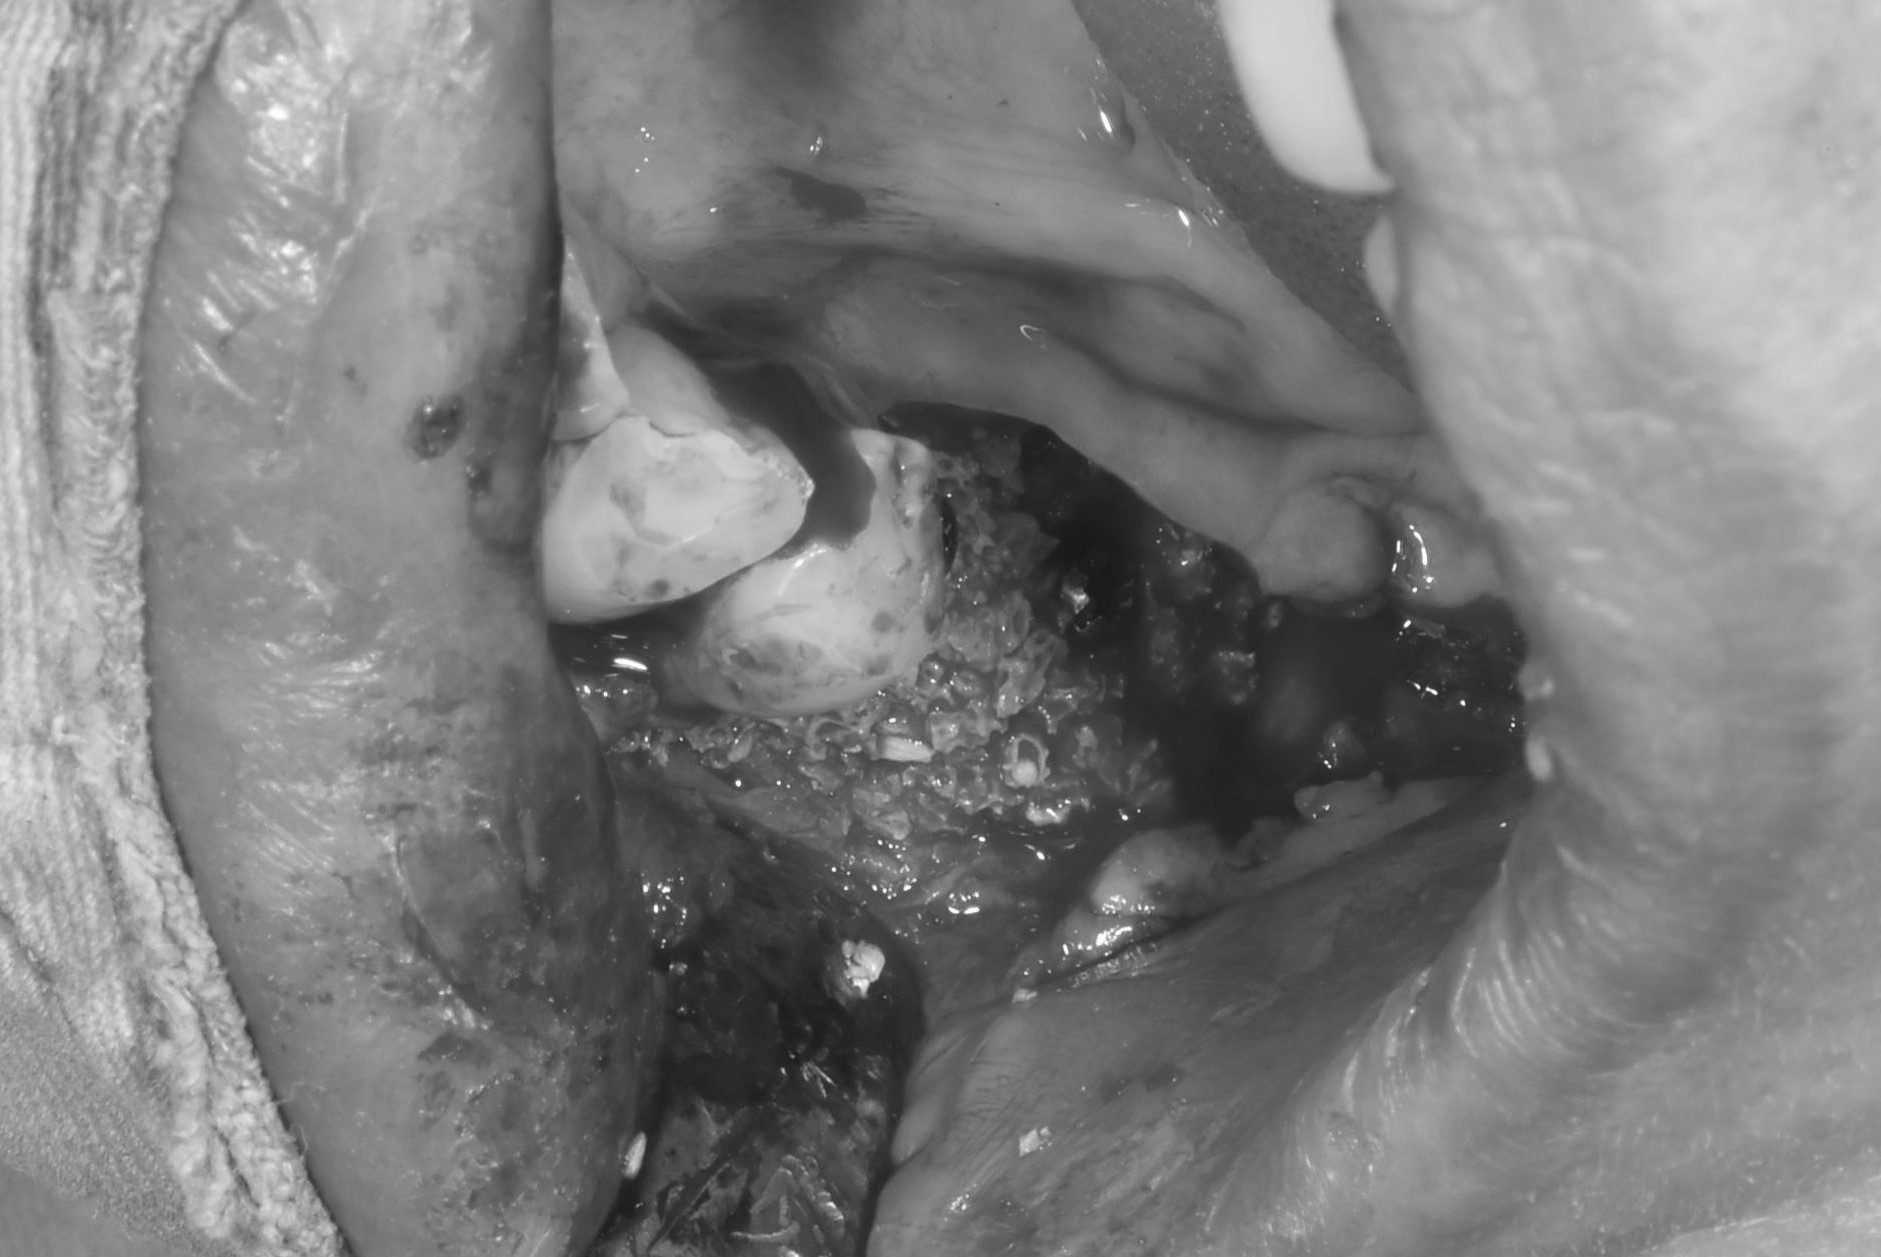

案例二

骨頭明顯凹陷